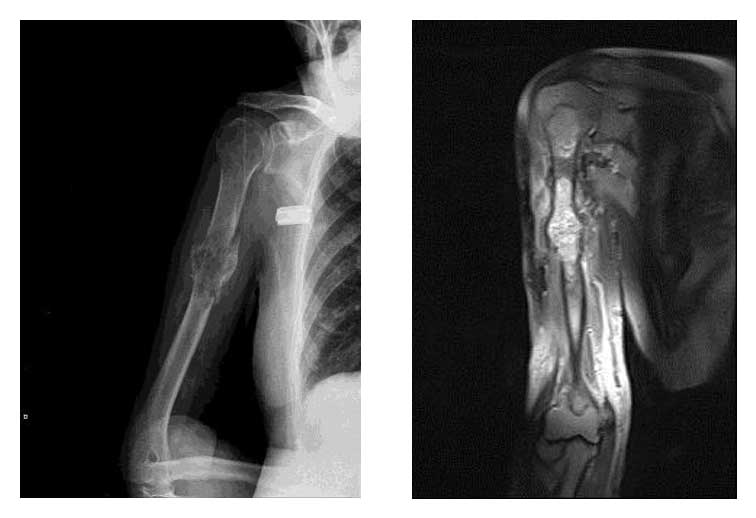

Ameliyat Öncesi: Röntgen ve MR’da sağ humerus orta kısımda yeniklik, kaynamamış kırık ve üst uca kadar yayılım gösteren metastaz odağı.